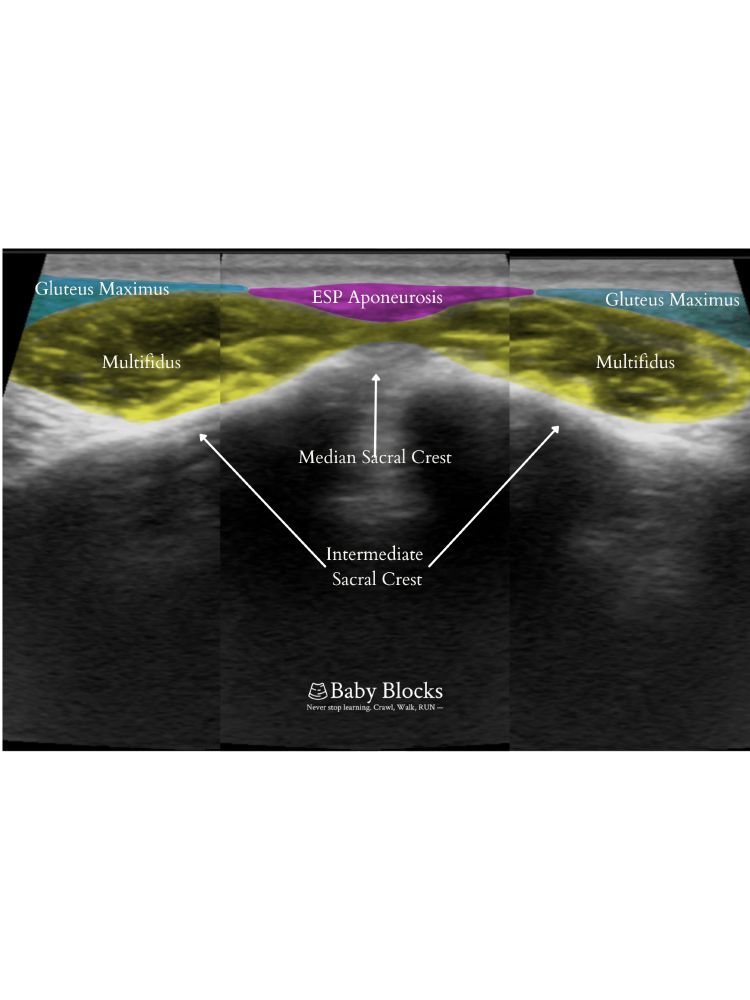

Day 5: The Sacral Multifidus/ESP Block targets dorsal rami for sacral & pelvic pain relief with minimal motor impairment. Its versatility makes it ideal for chronic pain & postop relief—and it’s our most popular regional page of 2024!

www.baby-blocks.com/block-detail...